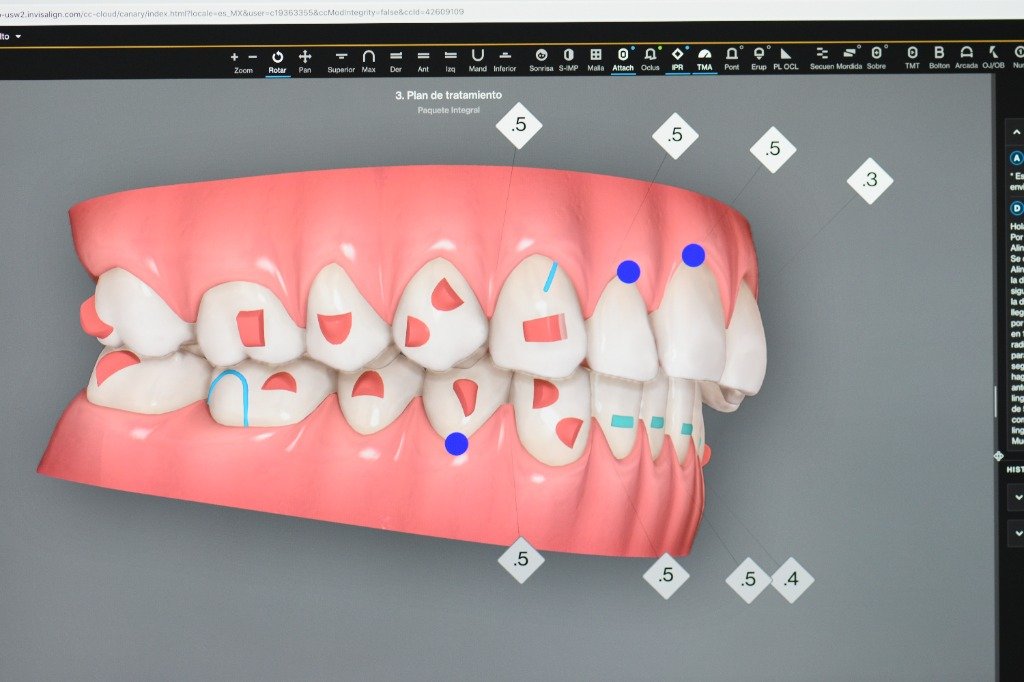

En la Clínica Mompell & Micó, sabemos que el primer paso para ofrecerte el mejor tratamiento es un diagnóstico completo y preciso. Con tecnología avanzada y un equipo especializado, aseguramos que cada detalle sea considerado para ofrecerte el mejor plan de tratamiento personalizado.